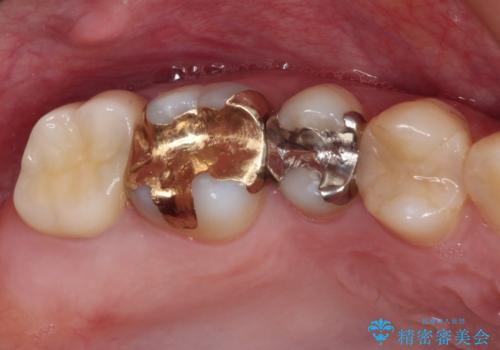

- 右上下の奥歯がむし歯でしみたり痛んだりするとのことで来院された患者様です。

下顎の奥歯は強い痛みを感じており、既に歯髄に不可逆的な炎症が起きていると診断されたため、根管治療の後にセラミッククラウンにて補綴治療を行うこととしました。

上顎の奥歯は最近銀歯による治療を行ったとのことでしたが、適合が不十分であり隙間からしみていたため、適合の良いゴールドインレーにて修復治療を行うこととしました。